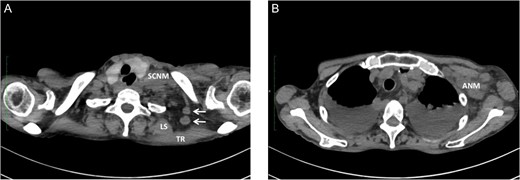

We have had three cases of this unusual LNM from cancer of the thoracic esophagus to date. Clinicopathological characteristics and survival are presented in Table 1. This unusual LNM developed after esophagectomy in two patients (cases 1 and 2, Fig. 2) and was found at presentation in a third patient (case 3, Fig. 3).

Metastasis of the supraclavicular nodes (SCNM), the nodes located between TR and LS (arrow) (A), and the axillary nodes (ANM) (B) developed 4 months after esophagectomy.